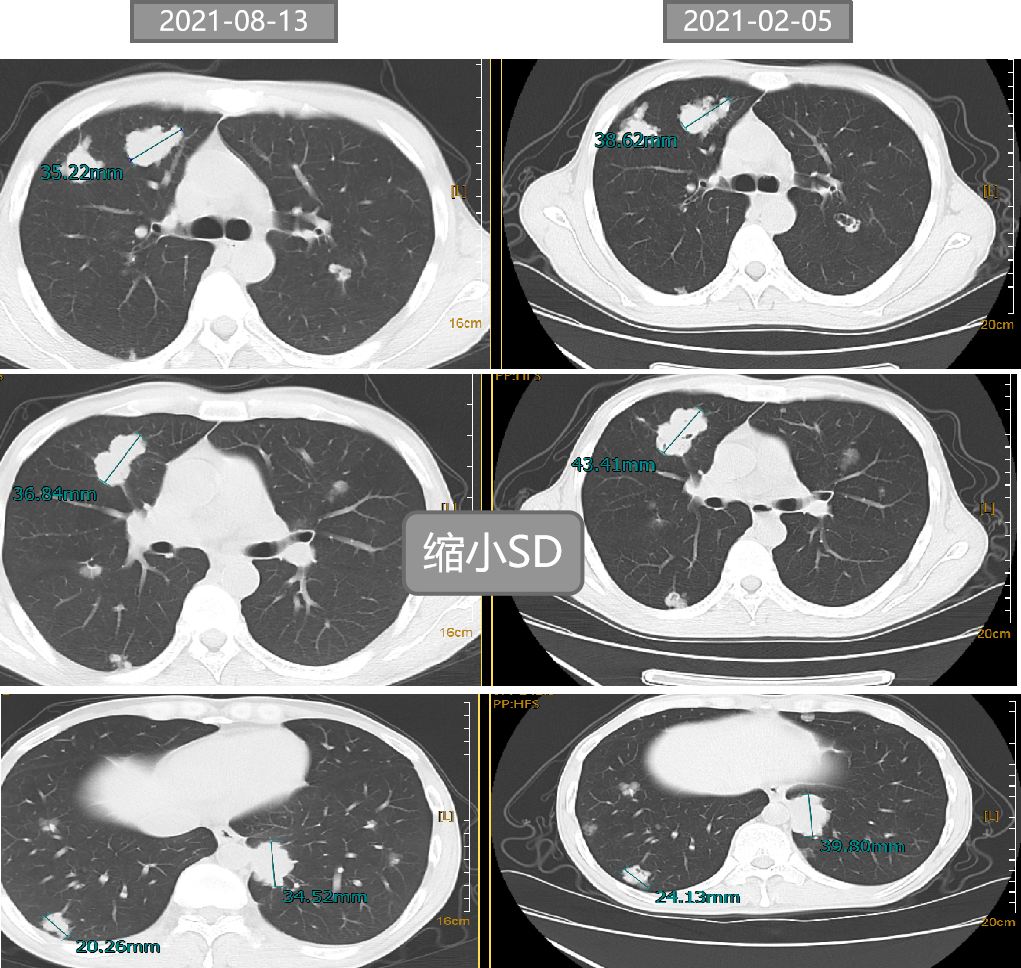

二 病例分享 专家简介 01 基本情况 刘某某,男性,28岁。 主诉:大便次数增多2月。 首诊时间:2018-07-03,北京大学人民医院。 既往史:右踝关节骨折术;痔疮病史。 个人史:无特殊。 家族史:其父为小细胞肺癌患者。 入院查体:ECOG 1分,无明显阳性体征。 02 初诊病史 肿瘤标志物:CEA 19.45 ng/ml。 肠镜及病理:直肠(距肛门约8cm处),直肠腺癌。 胸腹盆增强CT:1.双肺多发结节,考虑转移瘤可能性大;2.肝S6段异常密度灶;3.下段直肠癌可能性大。 盆腔增强MRI:(中位)直肠癌、T(3b)、N(2b)、癌结节(0)、CRM(阳性)、EMVI(阴性)、非区域淋巴结(阴性)。 上腹部增强MRI:肝S6段小结节,不典型血管瘤可能大。 初步诊断: 1.直肠癌(cT3N2bM1aIVA期 )肺转移; 2.痔疮; 3.右踝关节骨折术后; 4.肝血管瘤。 03 治疗方案 外院:XELOX。 我院首诊:2018-07-18。 免疫组化:MLH1(+),PMS2(+),MSH2(+),MSH6(+)。 2018-07-25至2018-09-26 XELOX *2+局部放疗*25f,PD。 基因检测(2018-10-23):KRAS、NRAS、BRAF基因均未见突变。 二线治疗:2018-10-18至2019-03-01 贝伐珠单抗+FOLFIRI*9 (SD→PD)。 疗效评估 三线治疗:2019-03-28至2019-07-23 西妥昔单抗+伊立替康+雷替曲塞*6(SD→PD)。 疗效评估 2019-07-25 瑞戈非尼 80mg po。 2019-09-26 复查:SD,瑞戈非尼 120mg po。 2019-11-21 复查:PD,瑞戈非尼 160mg po。 疗效评估 2019-12-19 至2020-09-24 信迪利单抗 200mg q3w +瑞戈非尼80mg po d1-d21 q4w。 2020年 ASCO 更新的瑞戈非尼+纳武利尤单抗(regorafenib+nivolumab)在晚期结直肠癌或胃癌患者中的Ib期临床试验(REGONIVO, EPOC1603)。 疗效评估 2020-09-26 盆腔增强MRI:直肠癌治疗后复查,与2020-05-10 MRI比较:直肠壁增厚程度较前似进展;直肠下段偏左侧新发不规则异常信号,考虑瘘管/脓肿形成。 考虑直肠下段脓肿,行抗感染治疗。 并于 2020-10-14 在气管插管全身麻醉下行腹腔镜下乙状结肠造口术。 2020-11-06 至2021-02-05 信迪利单抗200mg q3w+呋喹替尼3mg d1-21 q4w。 双肺多发转移瘤,对比 2020-11-04 CT较前增大、部分空洞形成。 TAS-102:新型口服细胞毒性药物 2021-V1版NCCN指南和2021 CSCO指南推荐更新:TAS-102±贝伐珠单抗(Bev)作为mCRC三线标准治疗。 2021-02-05 至今 TAS-102 60mg bid d1-5,d8-12,q4w 联合信迪利单抗200mg q3w。 不良反应 西妥昔单抗:皮疹; 瑞戈非尼:手足综合征; PD-1抑制剂:免疫性甲状腺炎; TAS-102:骨髓抑制(中性粒细胞IV度下降、贫血)。 04 诊疗小结